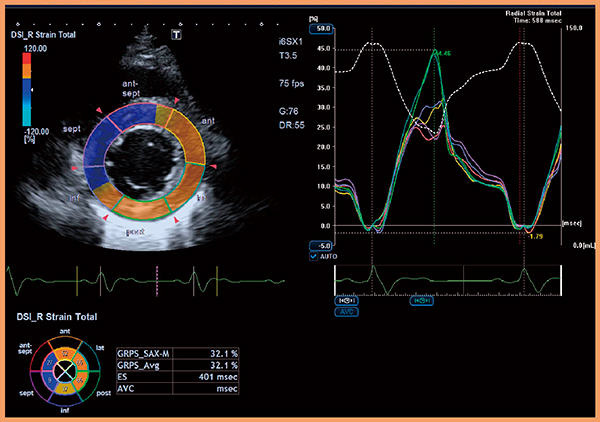

3D WMTでは,2D WMTの欠点である心拍による解析断面のズレの影響が克服され,心臓の動きを三次元的にとらえられるため,より正確に心機能を評価することが可能となる。本機能を右室解析用に発展させた“3D RV Tracking”では,右室を7分画に分割し,局所的な心筋収縮動態評価が可能となる(図8,9)。

図8 3D RV Trackingによる右室機能評価

(画像ご提供:杏林大学・坂田好美先生)

図9 3D RV Trackingによる右室7分割表示